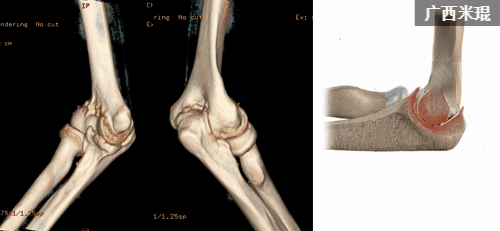

8.尺骨冠状突骨折

尺骨冠状突骨折既常见,也难处理,肘关节镜下可以清晰的显示尺骨冠状突,并能够进行骨折复位内固定,可以大大地简化治疗。